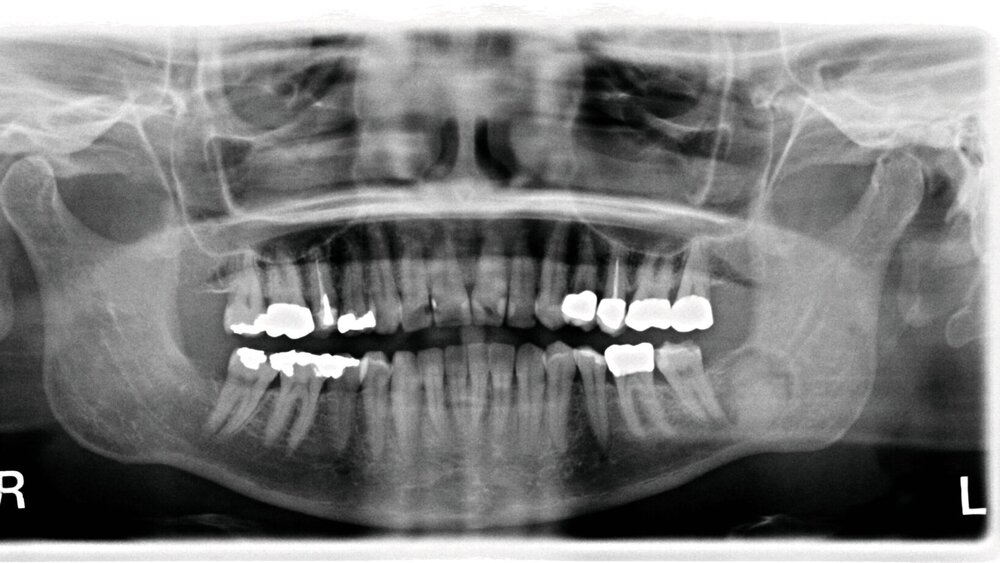

In der dreidimensionalen Bildgebung mit digitaler Volumentomografie (DVT) zeigte sich die intraossäre, scharf abgrenzbare, überwiegend homogen mineralisierte Raumforderung mit zirkulärem, hypodensem Randsaum. Der Nervus alveolaris inferior wurde durch die Läsion nach kranial verdrängt und subtotal ummauert (Abbildung 2). Zur Dignitätssicherung planten wir die vollständige Entfernung der Raumforderung unter Erhalt des Nervus alveolaris inferior in Intubationsnarkose. Eine ausgedehnte Resektion mit Unterkieferkontinuitätsdurchtrennung war aufgrund der unklaren Dignität zum Vorstellungszeitpunkt nicht indiziert.